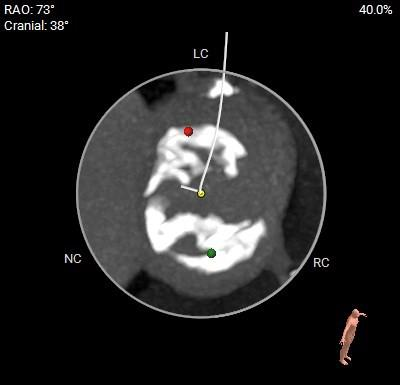

术前CT评估

主动脉根部测量

瓣环角度及弓角弓距

◇ 主动脉瓣环水平夹角52°,非横位心,主动脉弓角度较锐(43°)及弓距偏短;